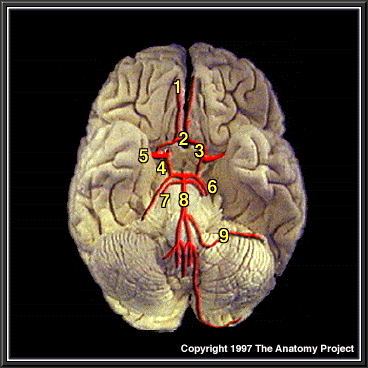

Brain Showing Arterial Supply, Inferior View

Anterior cerebral artery

Anterior communicating artery

Internal carotid artery

Posterior communicating artery

Middle cerebral artery

Posterior cerebral artery

Superior cerebellar artery

Basilar artery

Anterior inferior cerebellar artery